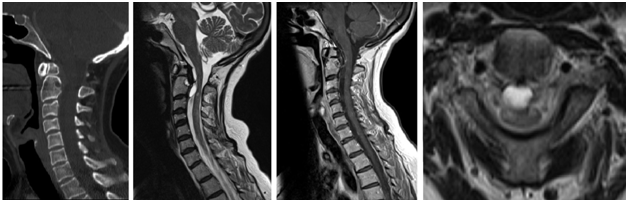

A 48-year-old woman presented with a two-month history of insidious onset of neck pain, paresthesia and right leg weakness, which progressed to affect her hands. Besides her dexterity dysfunction, her legs became progressively stiffer with worsening of gait. There was no history of previous trauma. On examination, she was myelopathic with significant hyper-reflexic signs including Hoffman’s sign and Babinski’s signs bilaterally. Cervical spine imaging had shown an os odontoideum with thickened ligaments and large synovial cyst compressing the spinal cord (Figure 1). In addition, multiple T2 hyper-intense foci were noticed through her cervical and thoracic cord. This was suspicious for possible concomitant autoimmune disease. Hence, an MRI of the brain was performed which was concerning for Multiple Sclerosis (MS) (Figure 2). A CSF analysis had confirmed the diagnosis with the presence of positive oligoclonal bands and an elevated IgG index.

Figure 1 A CT scan of the cervical spine demonstrates an os odontoideum with dorsal osteolytic dens related to degenerative joint space.

A. The MRI showed a synovial cyst with rostral and ventral extension.

B. A cyst wall showed some enhancement after gadolinium infusion.

C. Note the significant mass effect over the spinal cord along with cord signal hyper-intensity adjacent to the cyst level as well as across the caudal cervical cord.

D. [C: Cyst, SP: Spinal cord].